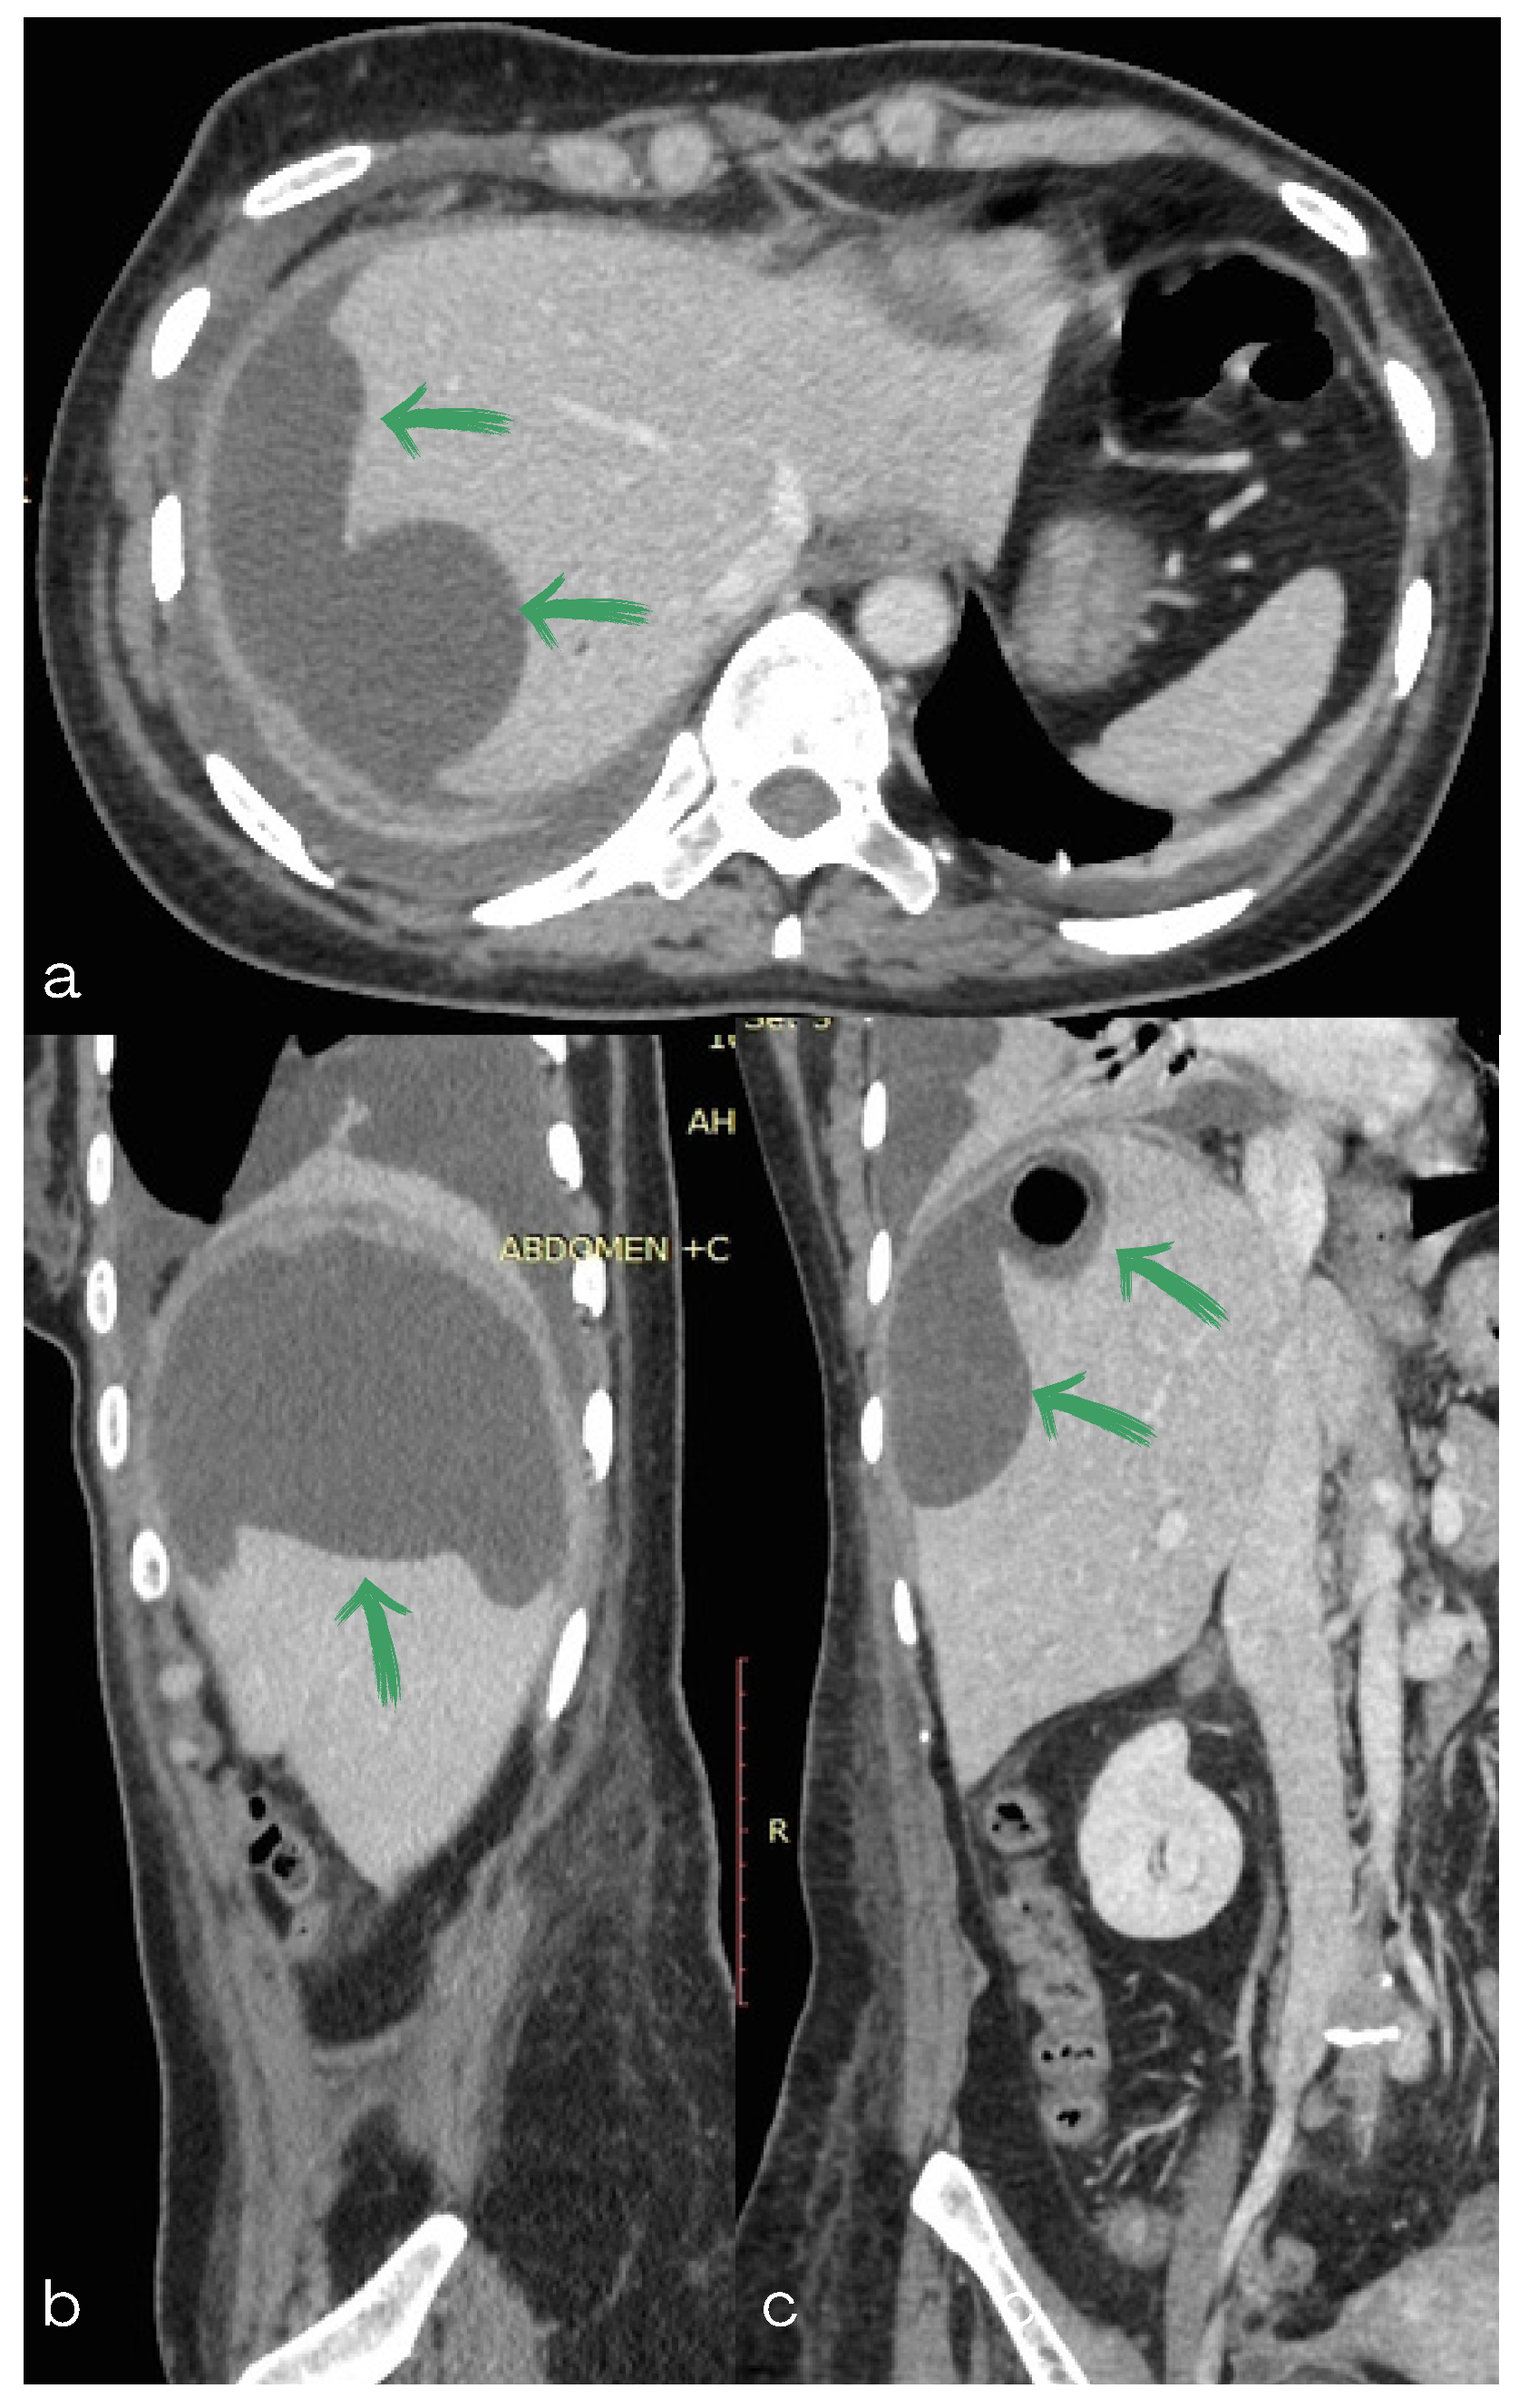

2. Case Report